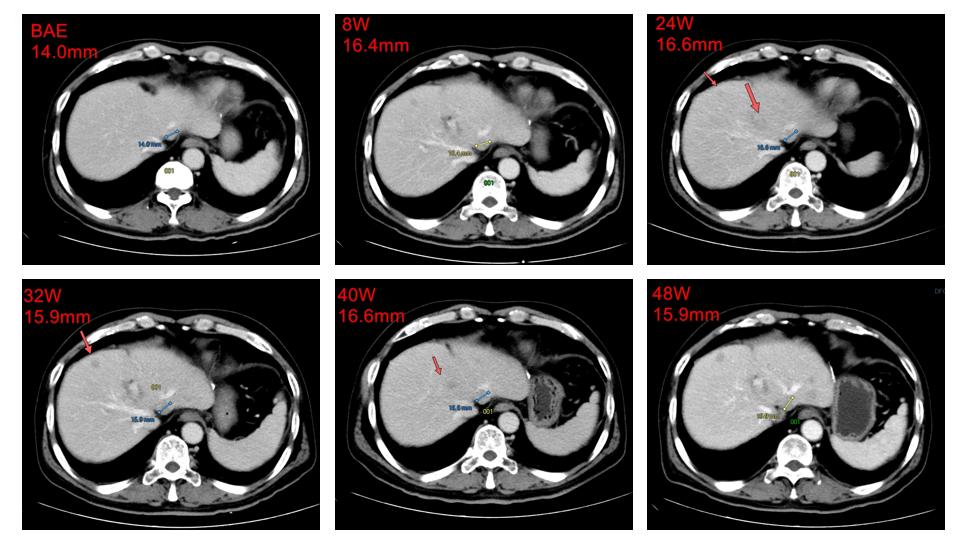

2016年4月13日,接受原发肝癌切除术,术程顺利。术后复查确认复发。2016年12月30日,首次服用多纳非尼(0.2g,每日两次)治疗,8周后经疗效评估为疾病稳定(SD)。随后继续使用,靶病灶持续稳定。经独立评审委员会(IRC)评估的无进展生存期(PFS)为7.5个月,而由研究者评估的PFS为11.2个月。

肝左叶靶病灶影像学改变:8-48W被评为SD